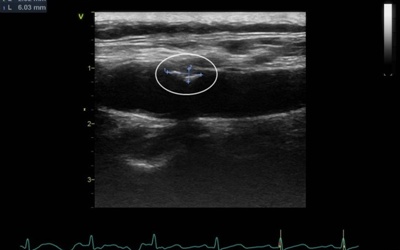

경동맥 초음파 검사는 목 부위에 위치한 경동맥의 상태를 실시간으로 확인할 수 있는 비침습적인 검사 방법입니다. 초음파를 이용하여 혈관 벽의 두께, 혈액의 흐름, 혈관 내 플라크(혈전)의 존재 여부 등을 파악할 수 있습니다. 마치 도로 위에 설치된 CCTV처럼, 혈관 속 상황을 안전하게 들여다보는 것이죠. 검사 과정은 간단하며, 통증이나 불편함이 거의 없어 누구나 부담 없이 받을 수 있습니다.

경동맥 협착은 경동맥 내부에 플라크가 쌓여 혈관이 좁아지는 질환입니다. 혈관이 좁아지면 뇌로 가는 혈류량이 감소하여 뇌졸중의 위험이 증가합니다. 경동맥 초음파 검사를 통해 협착의 정도를 정확하게 파악하고, 필요한 경우 약물 치료나 수술적 치료를 통해 뇌졸중을 예방할 수 있습니다.

경동맥 박리는 경동맥 혈관 벽이 찢어지는 질환입니다. 혈관 벽이 찢어지면 혈액이 혈관 벽 안으로 들어가 혈관을 막거나 혈전을 형성하여 뇌졸중을 유발할 수 있습니다. 경동맥 초음파 검사를 통해 박리된 혈관 벽을 확인하고, 신속하게 치료를 시작하여 뇌졸중을 예방해야 합니다.

경동맥 동맥류는 경동맥 혈관 벽이 약해져 혈관이 부풀어 오르는 질환입니다. 동맥류가 파열되면 출혈이 발생하여 생명을 위협할 수 있습니다. 경동맥 초음파 검사를 통해 동맥류의 크기와 위치를 파악하고, 파열 위험이 높은 경우 수술적 치료를 고려해야 합니다.